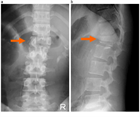

1. 頭蓋頚椎、頚胸椎、胸腰椎の各移行部での脊椎損傷は他の臓器との重なりが多く、単純X線では見落とされることがあり、CTによる評価が推奨される。

1. 高齢化に伴い強直性脊柱や骨粗鬆症を基盤とした脊椎損傷の比率が上昇しており、その病態、損傷形態に応じた治療法、手術法が求められる[1]